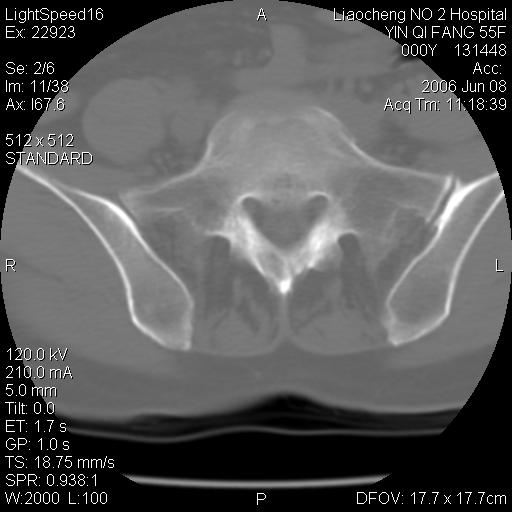

女,55岁,十余年前骶尾骨摔伤,x线平片诊断骶骨裂纹骨折,现在骶尾部又疼痛2月,x线怀疑骶骨左下部骨质破坏。大家看看,是不是先天变异。正常人不是只有4个骶孔吗?怎么此病例有5个?

两侧骶髂关节炎,确实做得很漂亮

众口一词啊,图象确实漂亮,羡煞人也!右侧骶髂关节间隙变窄,相对缘增生硬化,髂骨侧增生明显。左侧轻微类似改变,考虑双侧骶髂关节炎。余未见异常。

考虑双侧骶髂关节炎。余未见异常。

支持骶髂关节炎,3d做得很漂亮!!!!

图象很漂亮,骶骨未见异常,感觉右侧骶髂关节髂骨面密度增高,不知是否异常?

五个孔也是正常的呀;